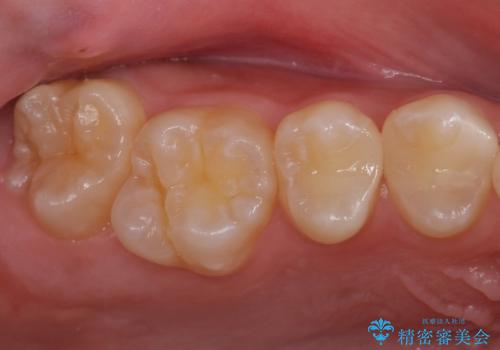

歯と歯の間の虫歯 セラミックインレーでの治療

- 検査の結果奥歯と奥歯の間に虫歯が確認されました。

虫歯を取り除いた後、セラミックインレーで修復していきます。

- 右上45 セラミックインレー 77,000円×2本費用は治療当時の料金となります

適合の良い修復物を装着することで今後の虫歯リスクを抑えることができます。